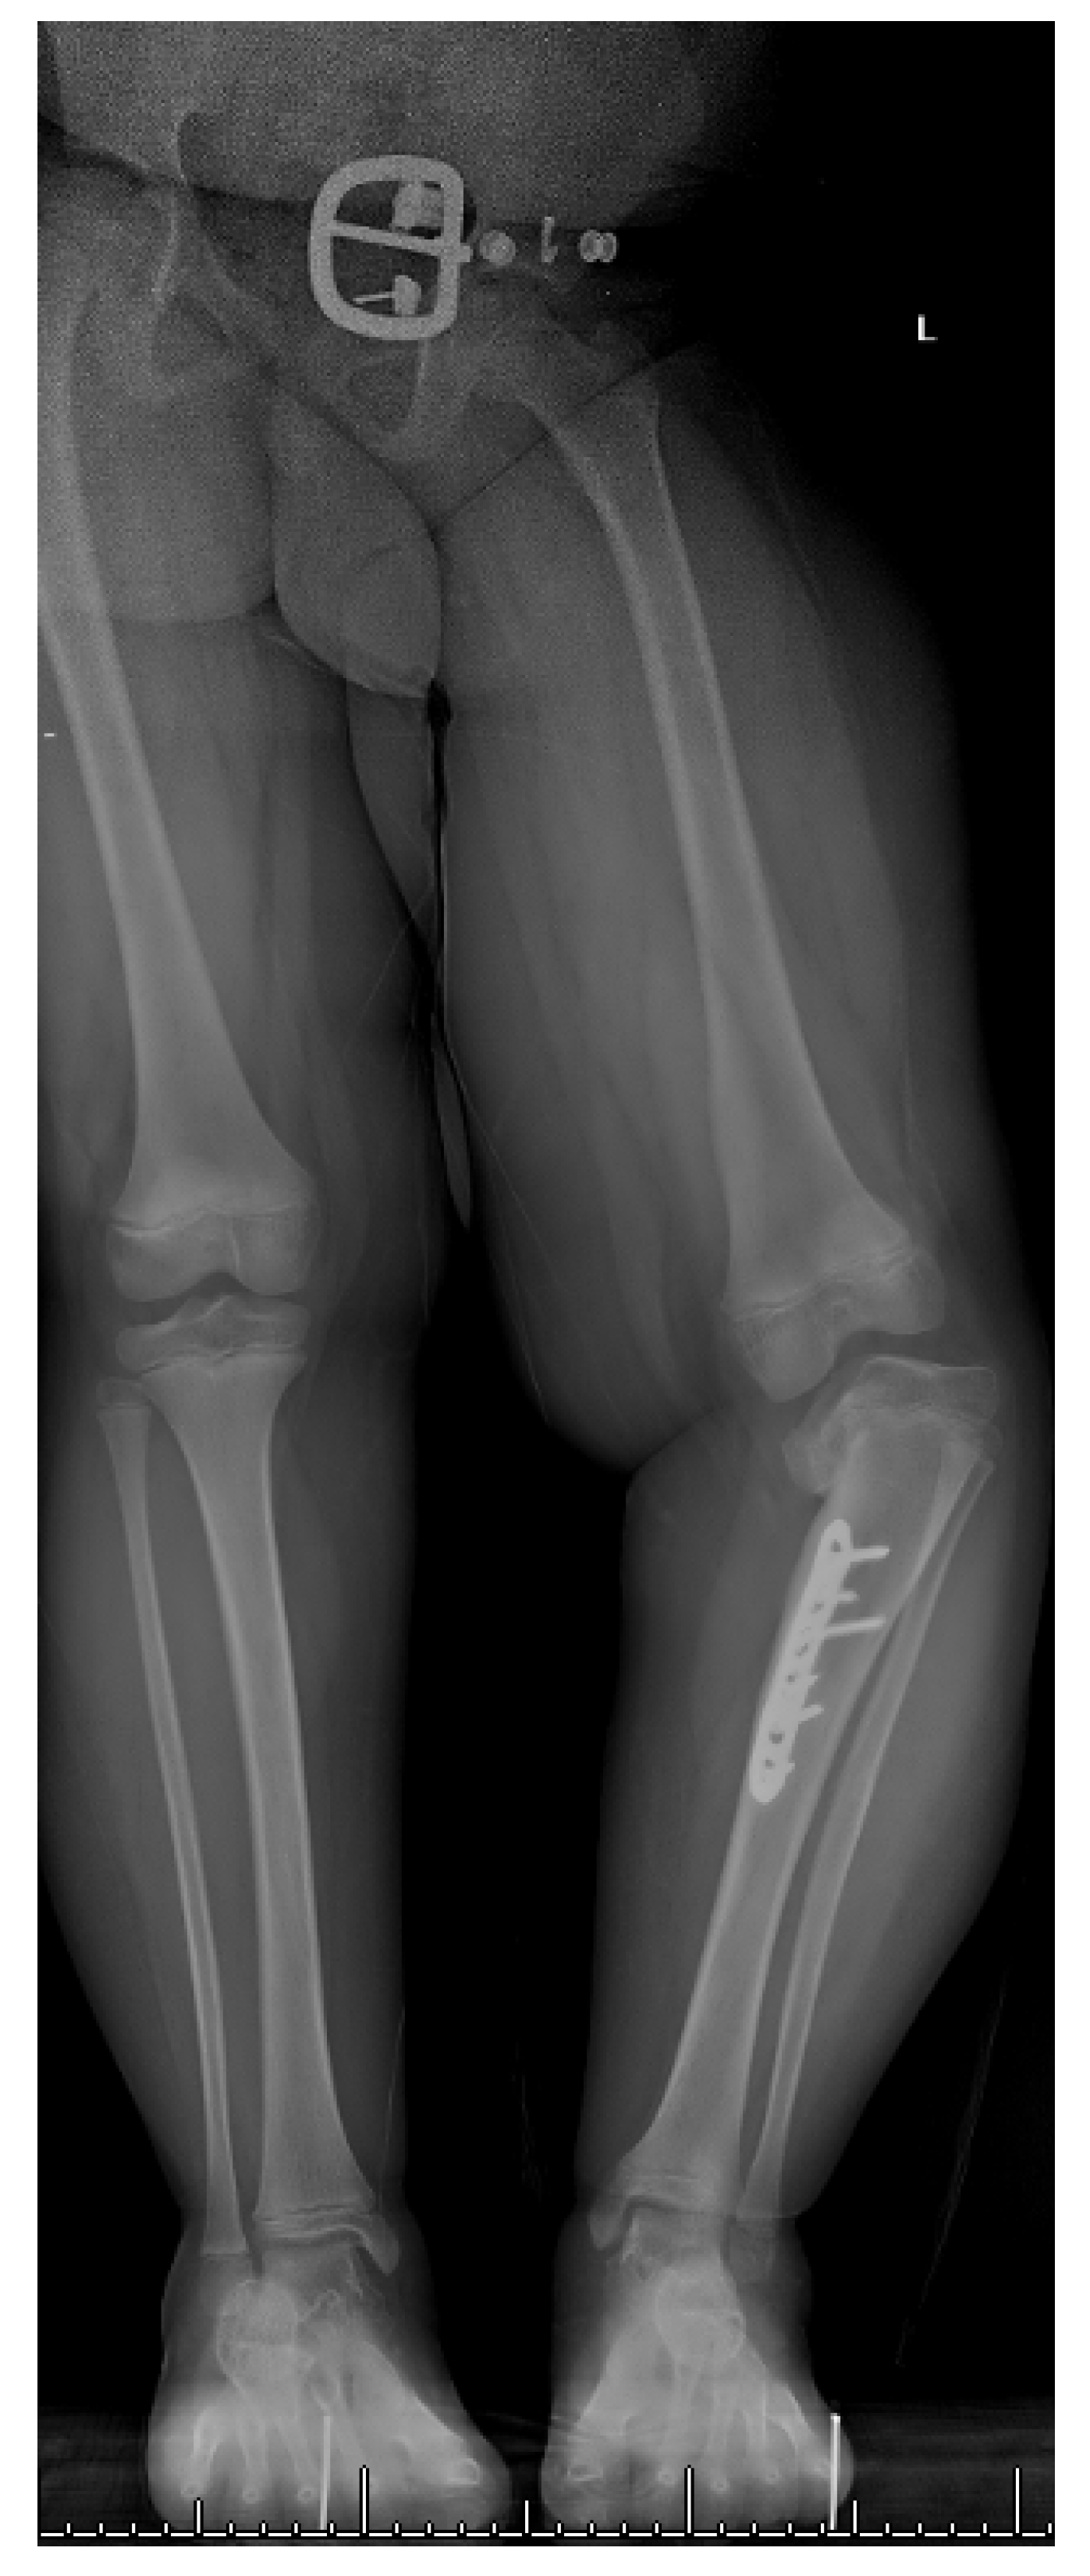

13. Osteotomies with Acute Correction

17. Gradual Correction with External Fixation